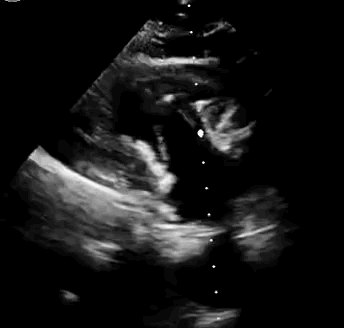

上海中山醫(yī)院葛均波院士、錢菊英院長、周達新教授、潘文志教授、潘翠珍教授、李偉教授共同完成此次臨床前研究。術后葛均波院士對Lux-Valve Plus的器械操作性能給予了高度評價,DSA和超聲影像也顯示出在本次研究中Lux-Valve Plus的安全性和有效性俱佳。

本次臨床前研究經(jīng)右側頸靜脈置入LuX-Valve Plus輸送系統(tǒng)可調彎鞘管,在DSA及超聲引導下將人工三尖瓣瓣膜植入到原有三尖瓣位置,利用獨特的錨定技術將人工瓣膜支架可靠固定在預定的位置。